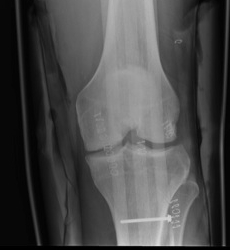

4. Meniscal Root Repair

Definition

- tear of insertion of posterior horn of meniscus

- difficult to fix

- must repair down to bone

Technique

- ACL guide

- drill hole up into mensical root insertion

- use suture passer to secure meniscal root

- retrieve sutures down through bone tunnel in tibia

- tie over screw post